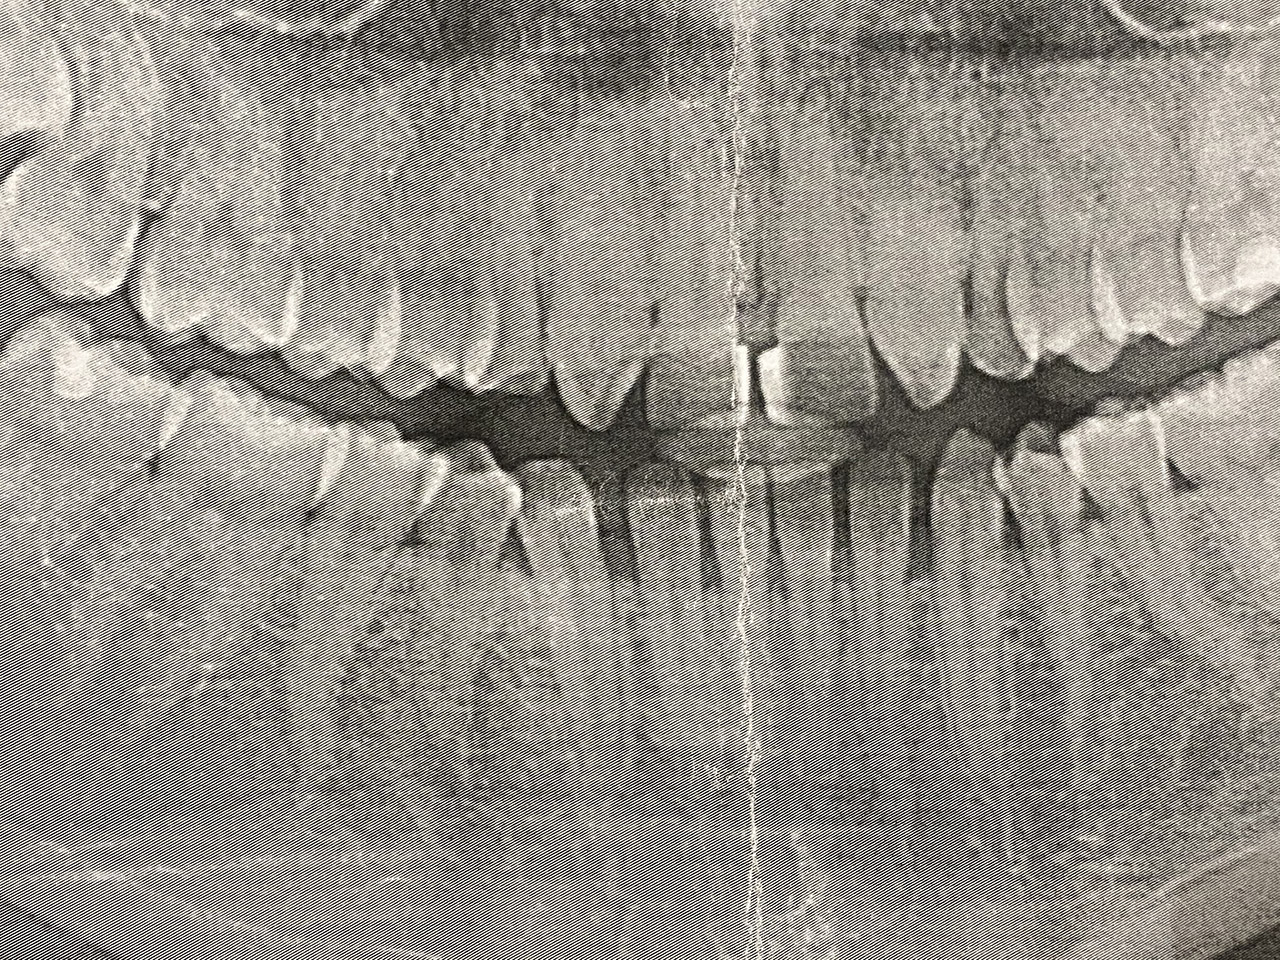

Wurzelbehandlung/Endodontie:

Massiver Paro-/Endodefekt bei den Zähnen 38&37. Extraktion von 38 (Weisheitszahn) und Wurzelbehandlung von 37 (4 Kanäle). Defekt vollständig ausgeheilt.